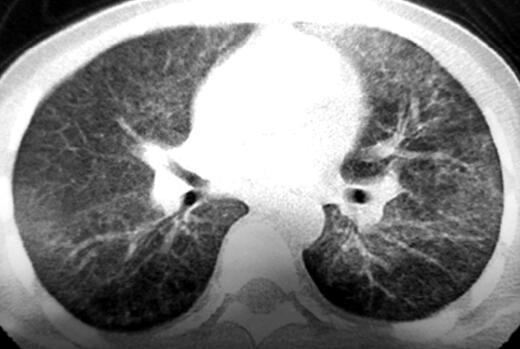

6.胸部HRCT:双肺多发磨玻璃影(如图3、图4)。

图4

2.肺部HRCT结果为弥漫性肺间质性改变,常见于巨细胞病毒性肺炎、过敏性肺炎、淋巴细胞间质性肺炎、肺泡蛋白沉积症等,但①患者无过敏原接触史,血常规嗜酸性粒细胞正常,且过敏性肺炎发热少见,胸部CT多可见边缘模糊的小叶中央结节,此病例不符,可以除外过敏性肺炎;②淋巴细胞间质性肺炎胸部CT多可见弥漫性磨玻璃影伴薄壁囊腔、小叶中央结节,淋巴结增大,此病例不符,暂不考虑淋巴细胞间质性肺炎;③肺泡蛋白沉积症症状隐匿,高热和中毒缺氧不常见,且胸部HRCT为磨玻璃影合并小叶间隔增厚(碎石路征),此病例不符,暂不考虑肺泡蛋白沉积症。目前不除外巨细胞病毒性肺炎。

3.动脉血气分析提示Ⅰ型呼吸衰竭,过度通气;结合血常规、痰病原学检查及胸部CT弥漫性磨玻璃影表现,进一步支持病原菌感染造成肺间质性炎症的诊断思路,目前病原菌尚不明确,且患者目前状态差,Ⅰ型呼吸衰竭,当前重要的是选择合适的药物进行经验性抗感染治疗,改善患者一般状态。